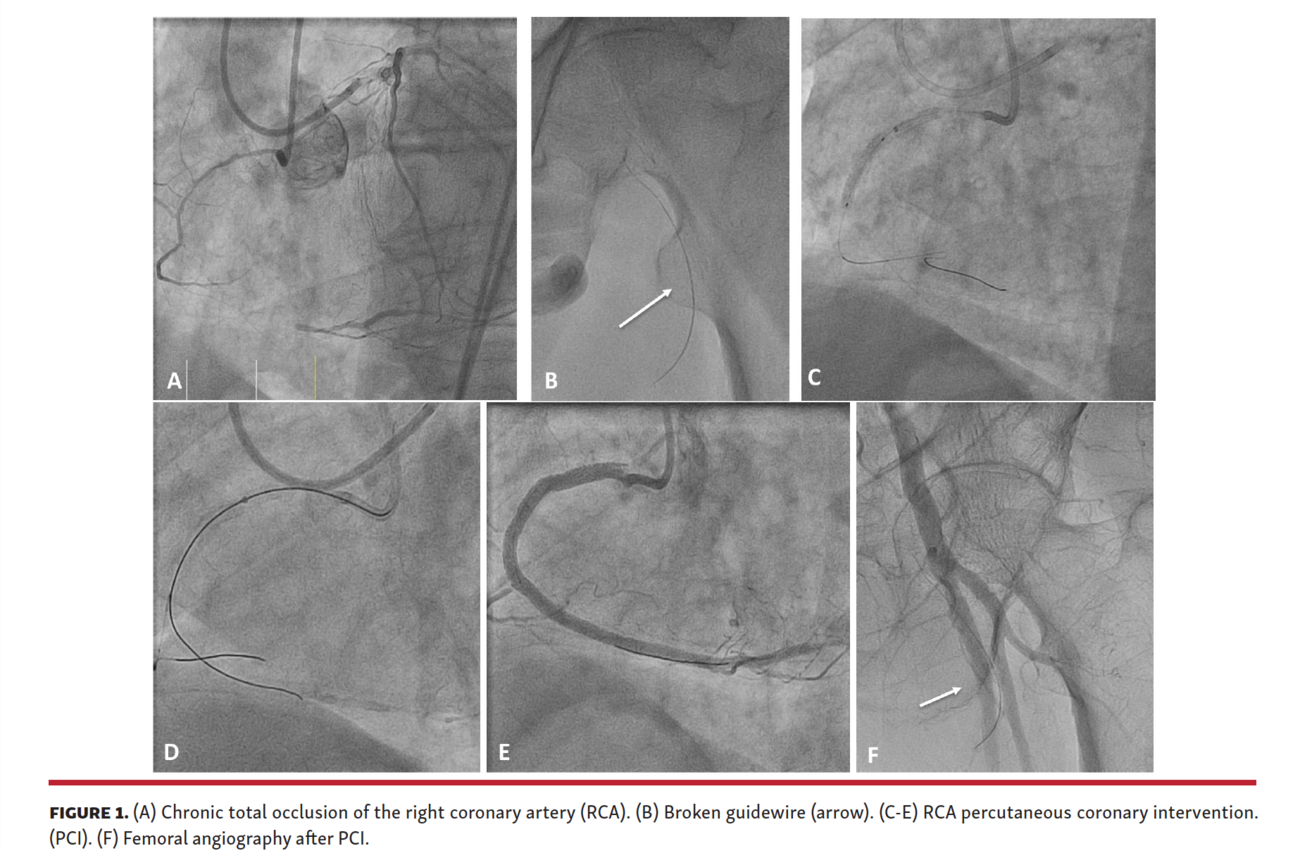

Traveling Wire After Chronic Total Occlusion Percutaneous Coronary Blood Pressure Chronic Total Occlusion Coronary cto is characterized by heavy atherosclerotic. Once an artery becomes 100% blocked, it is considered a coronary chronic total occlusion, or cto. Coronary arteries with severe blockages, up to 99%, can often be treated with traditional stenting procedure. People with cto may experience chest pain, shortness of breath, and fatigue, and they are also at increased risk for heart. Blood Pressure Chronic Total Occlusion.